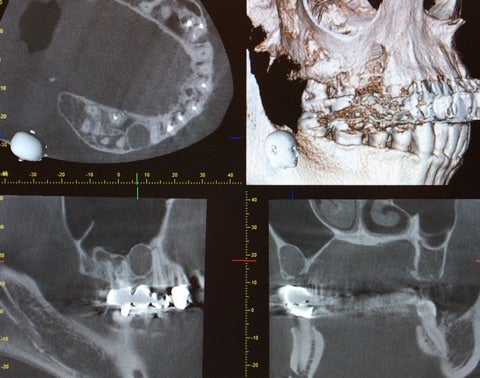

<CT画像①>

過去に根尖病巣を患い抜歯を行ってある部位に一致している事から術後性骨嚢胞の診断の下、嚢胞摘出術を行う事になりました。

今回も嚢胞は上顎洞に近接しているためピエゾサージェリーでの骨削を行い摘出を試みました。